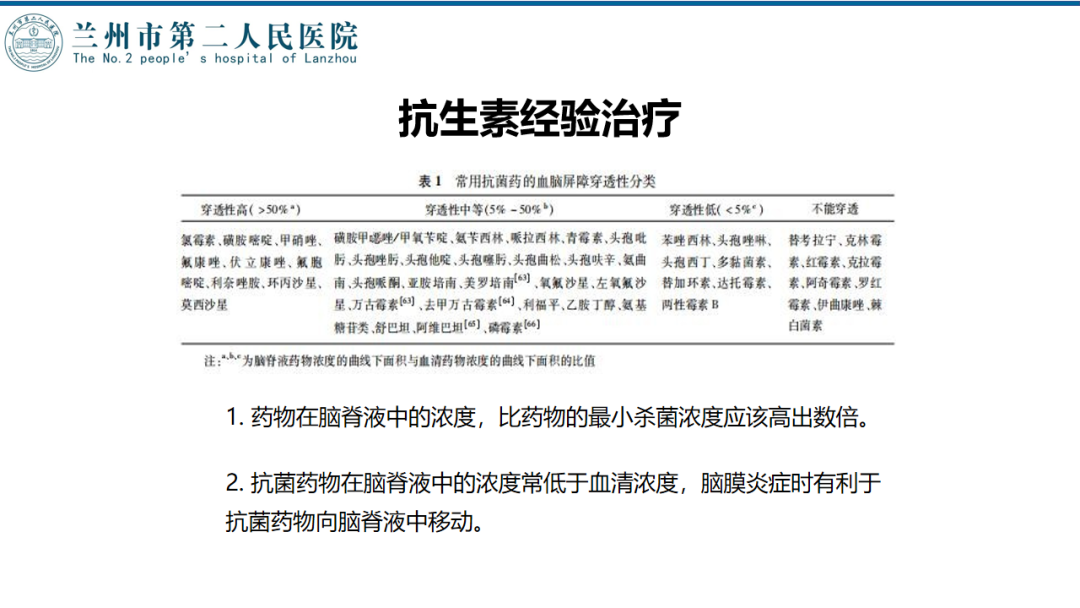

术后随访

术后CT

![]()

术后化验

2周后停抗生素